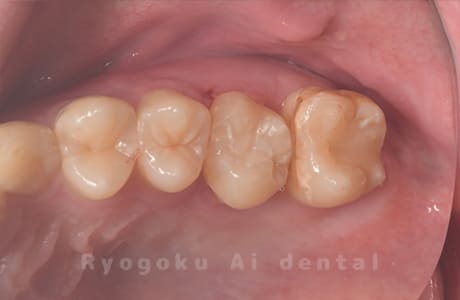

Case27

-

重度カリエス

歯牙移植咬合面術前 -

移植する親知らず

歯牙移植術直後咬合面

歯牙移植術後咬合面

歯牙移植術前側面

歯牙移植術中側面

歯牙移植術後側面

- 原因

- 重度カリエス

- 治療内容

- 自家歯牙移植、部分矯正

- 治療費用

- 220,000円(移植費用)

110,000円(部分矯正費用)

虫歯が大きく、保存不可能となった歯を上の親知らずと交換する自家歯牙移植を行いました。移植歯が小ぶりであったため、部分矯正を行い問題なく噛み合い、経過良好です。